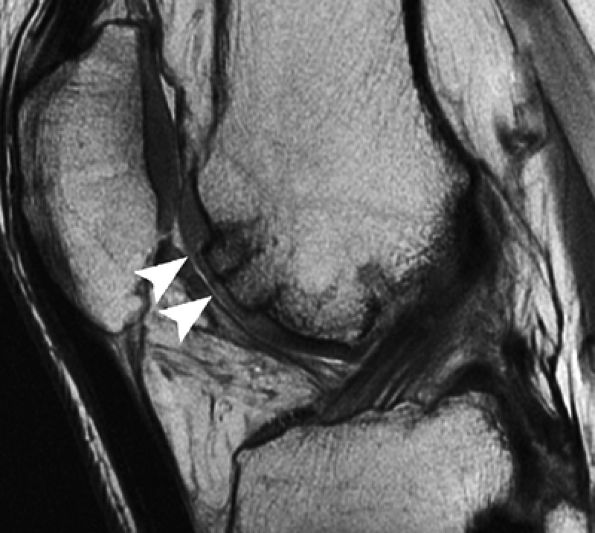

FIGURE 7.18 ● Prospective MR evaluation of a bone bruise in the knee of a 28-year-old man with a complete ACL tear. Sagittal fat-suppressed (A) and fast spin-echo (B) MR images obtained at the time of injury demonstrate characteristic bone marrow edema with compression of cartilage over the lateral femoral condyle (white arrow). A sagittal MR image obtained 19 months later (C) demonstrates proud subchondral bone with focal cartilage loss over the condyle (black arrow), as well as flap formation over the tibial plateau (arrowhead). (Reprinted by permission of SAGE Publications, Inc., from Am J Sports Med, in press.)